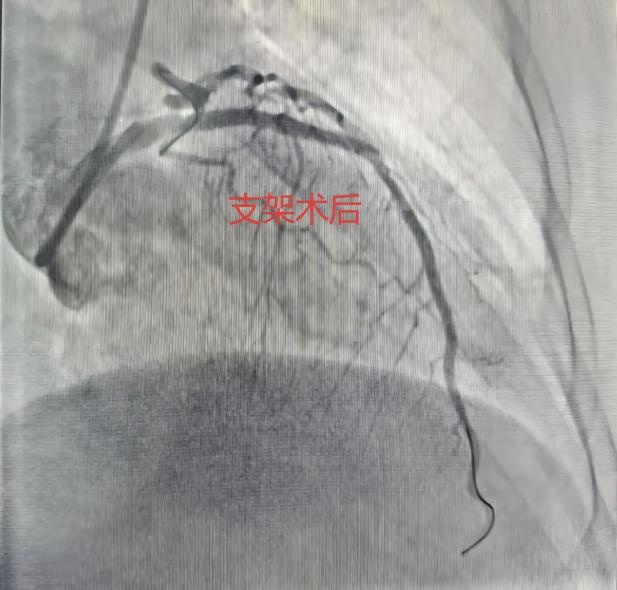

合肥市第三人民医院心血管内科副主任医师樊宗成向908新媒体讲述了当时的细节。急救人员测血压低,做心电图提示:急性广泛前壁心肌梗死!120通过胸痛中心绿色通道将她直接被送入导管室,冠脉造影显示,她的前降支(心脏最重要的血管之一)已经完全闭塞。植入支架、开通血管……经过近40分钟的抢救,她终于转危为安。周阿姨怎么也想不通:最冷的冬天感冒都没有,反而在春暖花开的3月住进了医院?这就是春天,一个万物复苏,却也暗藏“心”机的季节。